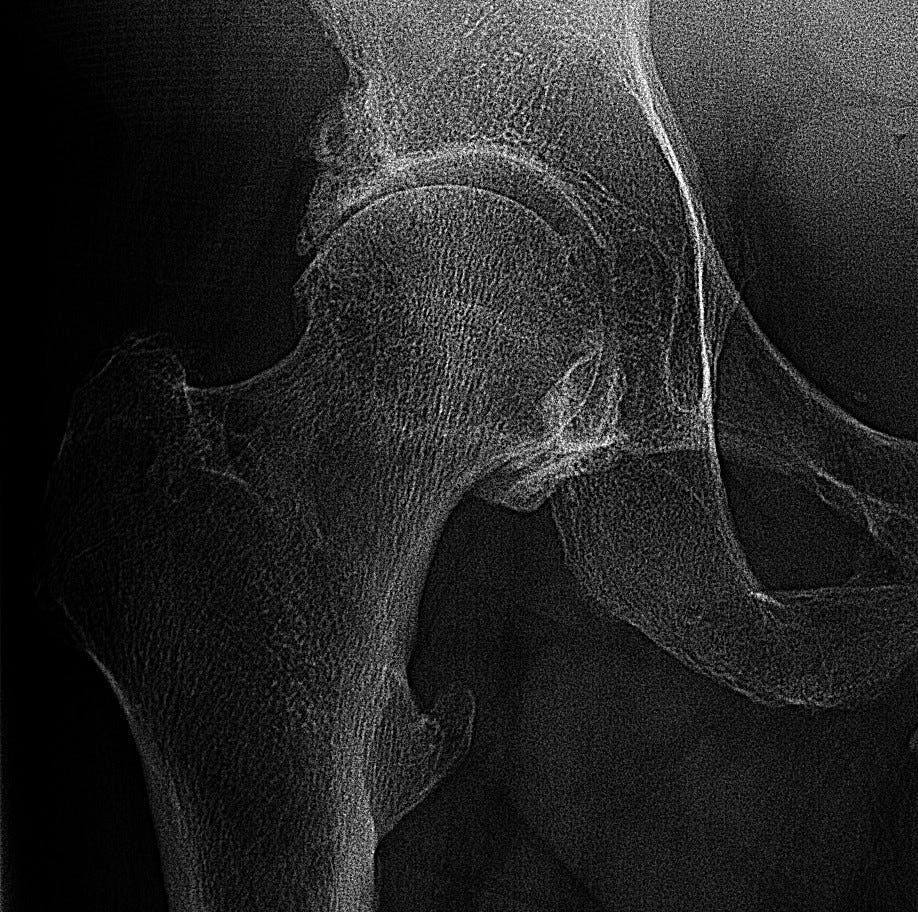

So he ordered up a couple of X-ray views of the area, and he didn’t even hesitate when he saw them. His terse summary: “Right hip osteoarthritis.”

I couldn’t believe it. I mean, I welcomed the diagnosis (shortly confirmed by others, like an orthopedic specialist) — I knew what it would mean: hip-replacement surgery.

Anyway, yes: it’s my hip. That mystery location, at the top inside of my thigh? It’s exactly where most patients with hip osteoarthritis feel pain.